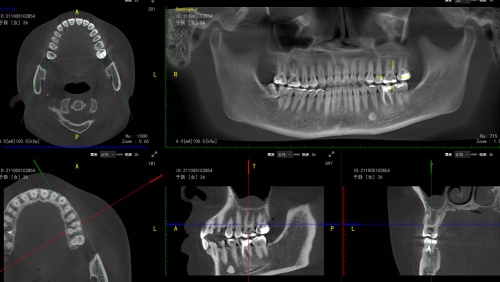

但随着材料、设备、技术的革新,传统根管治疗已被现代化根管治疗技术取代,尤其是牙科手术显微镜的应用为根管治疗带来了更多突破。显微镜下的根管治疗,可以将牙齿患病部分放大至2-30倍,拥有良好的照明环境,保证视野的稳定性,有利于观察牙齿根管内较细微的结构,确认治疗部位,在非常清晰的情况下进行操作,还能够检查治疗的情况。

同时,显微根管治疗可以对传统的根管治疗没有办法完成的,或者难以完成的,比如:侧支根管遗漏、钙化根管、塑化根管、侧壁穿孔及根管器械折断等,均能够进行准确的判断和精细治疗。显微根管治疗技术不仅大大提高了根管治疗的成功率,还意味着可以减少患者拔牙的可能,减少很多并发症。

显微根管治疗的数字可视化方案使得一张图片胜过千言万语,全面生动的可视化沟通帮助患者了解治疗过程,从而进一步提升治疗效果、降低沟通成本,使医患之间的信任更加牢固。同时,也更精确、更微创、成功率更高地清除患者病灶,保留天然牙,使患者得到最大程度的舒适化诊疗服务。